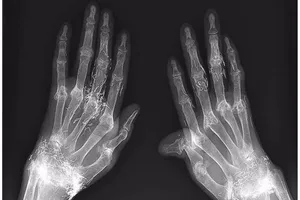

Dùng vàng khâu khớp tay để trị thấp khớp